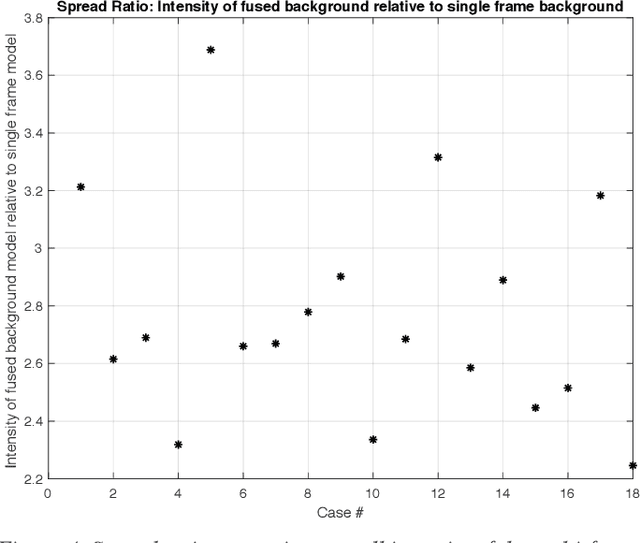

Molecularly targeted contrast enhanced ultrasound (mCEUS) is a clinically promising approach for early cancer detection through targeted imaging of VEGFR2 (KDR) receptors. We have developed computational enhancement techniques for mCEUS tailored to address the unique challenges of imaging contrast accumulation in humans. These techniques utilize dynamic analysis to distinguish molecularly bound contrast agent from other contrast-mode signal sources, enabling analysis of contrast agent accumulation to be performed during contrast bolus arrival when the signal due to molecular binding is strongest. Applied to the 18 human patient examinations of the first-in-human molecular ultrasound breast lesion study, computational enhancement improved the ability to differentiate between pathology-proven lesion and pathology-proven normal tissue in real-world human examination conditions that involved both patient and probe motion, with improvements in contrast ratio between lesion and normal tissue that in most cases exceed an order of magnitude (10x). Notably, computational enhancement eliminated a false positive result in which tissue leakage signal was misinterpreted by radiologists to be contrast agent accumulation.